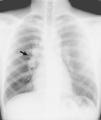

Medicina Clínica Tuberculosis ganglionar en paciente con masa cervical indolora

Tuberculosis ganglionar en paciente con masa cervical indolora

Lymph node tuberculosis in a patient with a painless cervical mass